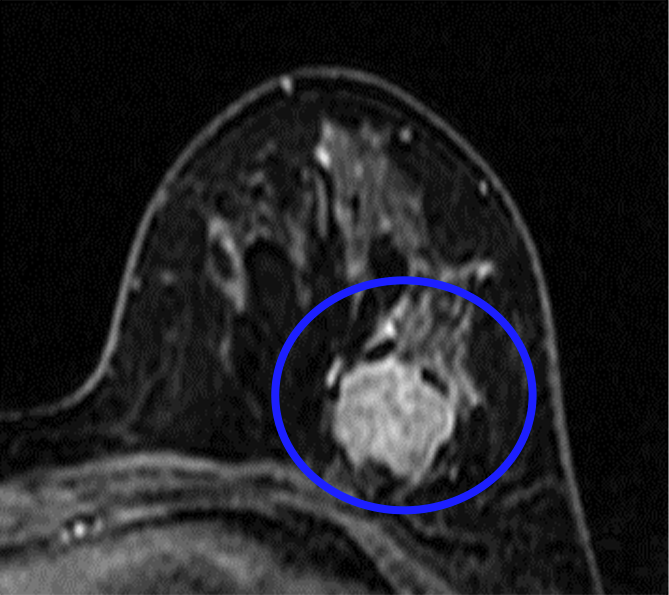

(図2) 術前治療で縮小した乳がん

- (治療前)造影MRI検査

- (治療後)造影MRI検査